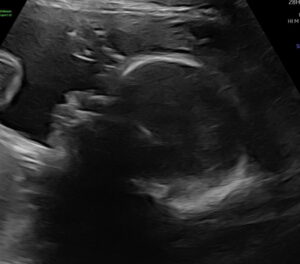

He Will Soon Be Here!

Baby boy on the way! I have a scheduled c-section for 12/10/25.